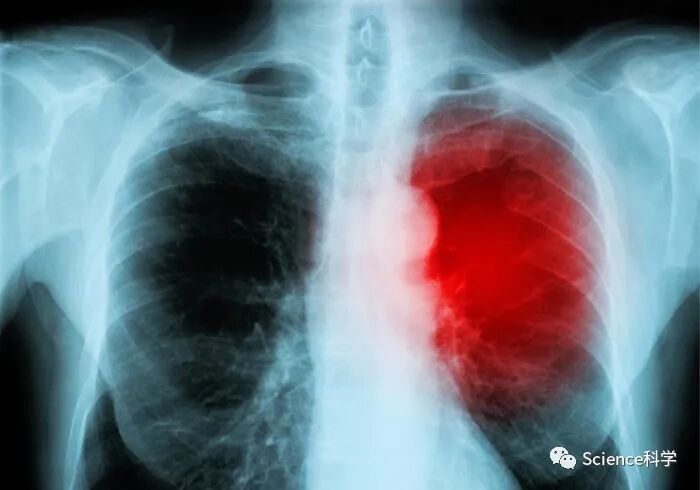

病毒是导致儿童心肌炎的最常见原因 而不是疫苗

心肌炎是心肌壁中间层的炎症,即心肌,它可以暂时或永久地削弱心肌和心脏的电气系统,而心脏的电气系统负责保持心脏的正常运转。在美国,每年约有10至20人被诊断患有心肌炎,在儿童中,发病率为10万分之1至2。尽管许多病例会自行解决或通过治疗导致完全康复,但严重的心肌炎可导致心力衰竭、心律异常、休克和猝死。心肌炎的体征和症状包括疲劳、呼吸急促、发烧、胸痛和心悸。

科学声明编写组主席、西雅图儿童医院心脏移植和心力衰竭服务部主任、西雅图华盛顿大学医学院儿科教授Yuk M. Law医学博士说:"心肌炎在儿童身上有明显的特征,对他们的终身健康有潜在影响。我们希望这份声明可以作为一个教育性的更新,并统一呼吁进行急需的研究,以更好地了解和治疗这一重要的儿科疾病。而且,鉴于最近公认的COVID-19感染后心肌炎的发生,以及COVID-19疫苗接种后疑似心肌炎病例的出现,本声明是临床医生和医护人员护理这些患者的资源。"

活检的直接组织检查是证明心肌炎存在的标准,这也可以确定是否存在病毒。然而,现在可以广泛使用侵入性较低的测试。心肌炎的其他筛查测试可能包括血液测试,测量表明心脏炎症或损伤的心脏酶的升高,包括肌红蛋白、肌钙蛋白和肌酸激酶。影像学检查包括超声心动图或心脏磁共振成像(MRI),以确定心脏是否有任何可见的损伤或心脏功能的异常情况。心电图(ECG)检查可以评估心律,并可能显示心脏受伤的迹象以及心包炎的迹象。心包炎通常与心肌炎有关,涉及心包的肿胀和炎症,心包是一种薄的、囊状的组织结构,围绕着心脏,将其固定并帮助其正常运作。